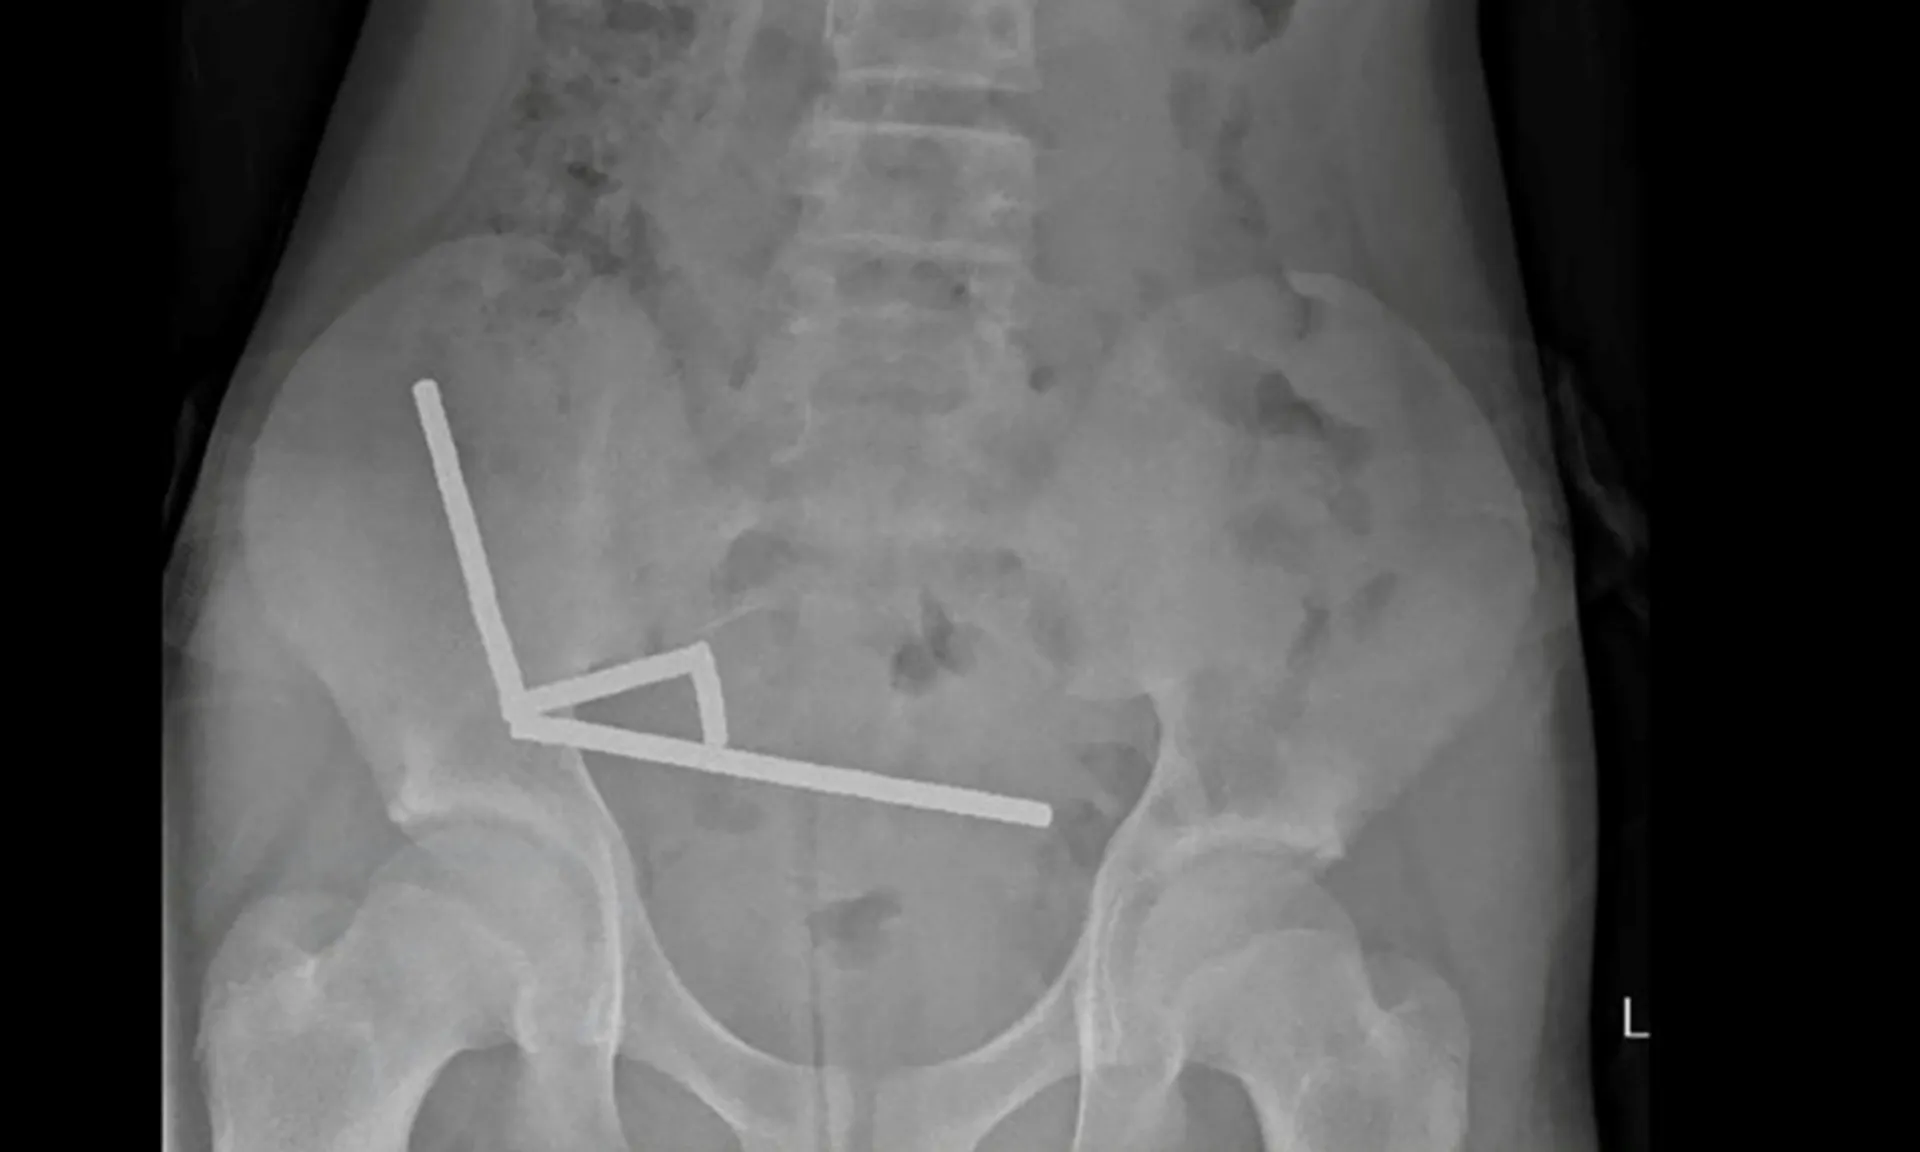

Phim chụp X-quang cho thấy một cảnh tượng đáng sợ: các viên nam châm đã dính lại với nhau thành bốn đường thẳng bên trong ruột của cậu bé.

Lực hút cực mạnh của nam châm đã gây ra tình trạng hoại tử (chết mô) nghiêm trọng tại bốn vùng trong ruột non và manh tràng (một phần của ruột già) của cậu bé.